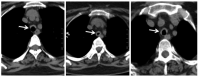

She was doing well for six months; however, she presented to emergency with history of cough, fever and wheeze for 15 days. On evaluation, she had type 2 respiratory failure and needed biphasic positive airway pressure support. Also, she was given high-dose steroids under antibiotics cover. HRCT of the chest showed worsening as expected. There was no improvement with the existing treatment even after three weeks. Patient continued having carbon dioxide retention with high respiratory rate and deterioration of sensorium despite noninvasive ventilation support. She also developed hospital-acquired infection. Discussion with the respiratory team and relatives ensued and decision for tracheal stenting was established (Figures 3 and 4).

Earlier stenting was avoided in view of long segment involvement. Post-procedure, she was put on ventilator and tracheostomized later in view of long-term ventilatory involvement. She was discharged after three weeks of hospital stay and later she suffered from post-procedure complications like tracheostomy site ulcer and its bleeding, subcutaneous emphysema and difficulty regaining activities of daily living. She was readmitted after a month with worsening of breathlessness and fever and was bound to have bilateral pneumonia. This time, she succumbed in view of sepsis and related acute kidney injury.